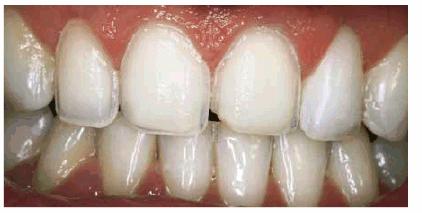

Figur 323s1823d e 18-3A: This young lady fractured her maxillary anterior incisors. Despite numerous bonding repairs, she continued to refracture the teeth. Because she also objected to the incisal translucency, she was treatment planned for three porcelain laminates.

Figur 323s1823d e 18-3E and F: Three porcelain laminates were placed on the central incisors and right lateral. The new laminates also achieved the objective to eliminate the incisal translucency.